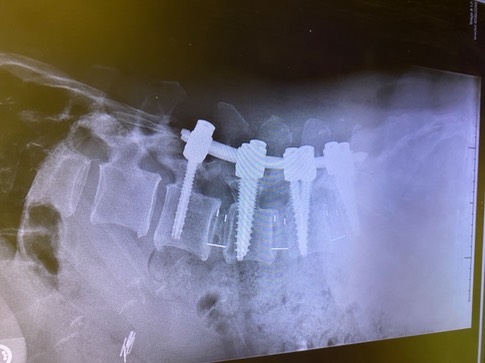

Honestly looking at the x-rays (Disclaimer* below is a picture of the x-ray showing the hardware), was a bit of a shock. While I knew as a nurse what had been place, it’s quite different to see the result. I wonder if Wolverine (X-Men) felt the same when he looked at what had been implanted in him? I’ve been asked if I can feel the hardware. Yes and No. Right now, I cannot feel the hardware if I run my fingers down my scar, that will probably change as inflammation continues to go down, due to my body structure. What I can feel is an odd sensation that is made up of muscles healing (they were cut during surgery) and a brick-like feeling, which is the hardware. There is a strange feeling as well which is the inability of that section of my spine to move.